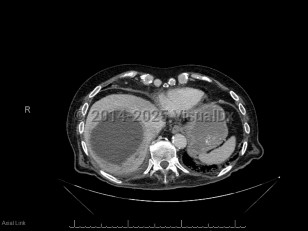

Pyogenic liver abscess

A pyogenic liver abscess is a collection of pus in the liver as the result of bacterial (or rarely fungal) infection.

Pyogenic liver abscess